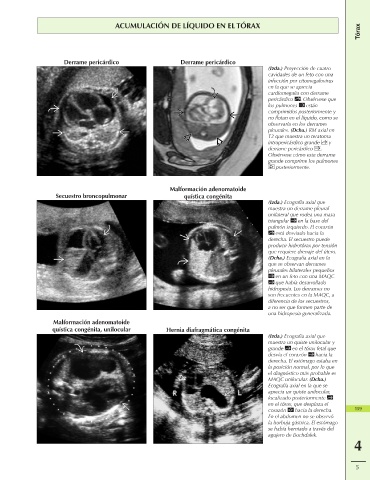

ACUMULACIÓN DE LÍQUIDO EN EL TÓRAX

Derrame pericárdico Derrame pericárdico

(Izda.) Proyección de cuatro

cavidades de un feto con una

infección por citomegalovirus

en la que se aprecia

cardiomegalia con derrame

pericárdico . Obsérvese que

los pulmones están

comprimidos posteriormente y

no flotan en el líquido, como se

observaría en los derrames

pleurales. (Dcha.) RM axial en

T2 que muestra un teratoma

intrapericárdico grande y

derrame pericárdico .

Obsérvese cómo este derrame

grande comprime los pulmones

posteriormente.

Malformación adenomatoide

Secuestro broncopulmonar quística congénita

(Izda.) Ecografía axial que

muestra un derrame pleural

unilateral que rodea una masa

triangular en la base del

pulmón izquierdo. El corazón

está desviado hacia la

derecha. El secuestro puede

producir hidrotórax por tensión

que requiere drenaje del útero.

(Dcha.) Ecografía axial en la

que se observan derrames

pleurales bilaterales pequeños

en un feto con una MAQC

que había desarrollado

hidropesía. Los derrames no

son frecuentes en la MAQC, a

diferencia de los secuestros,

a no ser que formen parte de

una hidropesía generalizada.

quística congénita, unilocular Hernia diafragmática congénita

muestra un quiste unilocular y

grande en el tórax fetal que

desvía el corazón hacia la

derecha. El estómago estaba en

la posición normal, por lo que

el diagnóstico más probable es

MAQC unilocular. (Dcha.)

Ecografía axial en la que se

aprecia un quiste unilocular,

localizado posteriormente

en el tórax, que desplaza el

corazón hacia la derecha. 159

En el abdomen no se observó

la burbuja gástrica. El estómago

se había herniado a través del

agujero de Bochdalek.